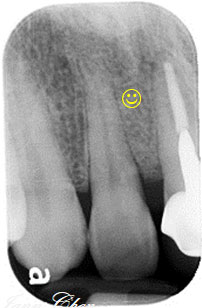

治療後

恢復健康牙齦

牙周再生成功